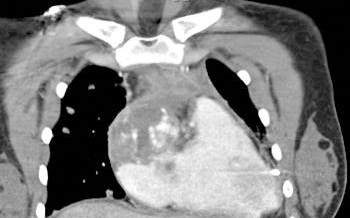

CT Chest: A mass is centered in the epicardium of the right atrial wall. It involves the pericardium and has extended through the myocardium to fill the right atrium. A small pericardial effusion exists. There is a small right pleural effusion, a heterogeneous appearance of the liver, and a small volume ascites. Numerous small masses are seen in the lung fields.